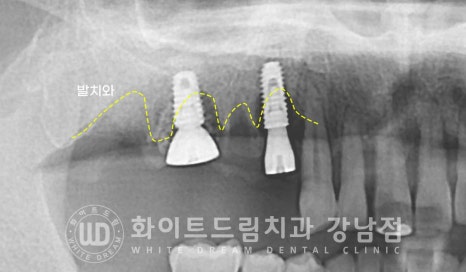

임플란트 식립 후 x-ray 사진입니다.

아직은 치아가 빠진 빈 공간, 발치와가 눈으로 확인이 됩니다.

이 발치와는 시간이 지나면서 잇몸뼈로 채워지게 되는데

임플란트 주위로 잇몸뼈가 두툼하게 잘 형성될 수 있도록

임플란트 식립 후 남은 빈 공간은 뼈이식재를 함께 넣고

봉합하면 큰 수술은 끝나게 됩니다.

24.04.29 수술